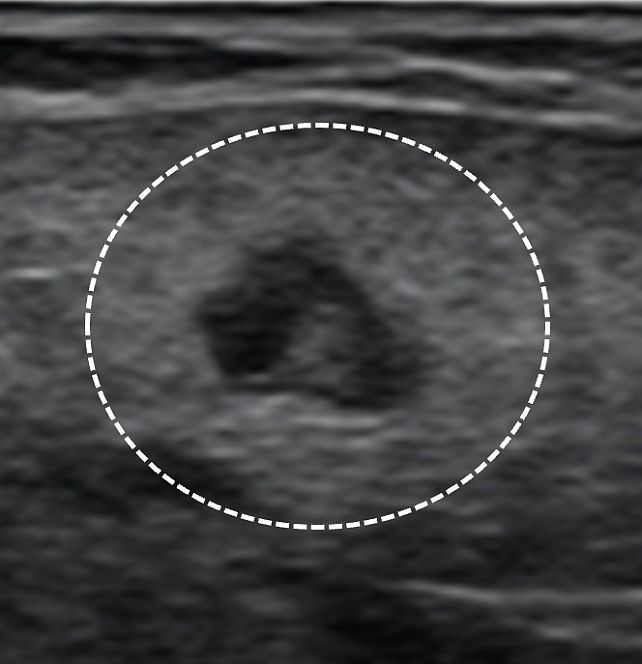

9

Perinodal hyperechogenic ring around the lymph node (dashed circle).